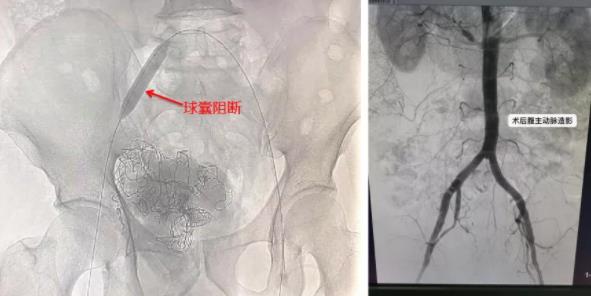

李建国主任当即立断开通绿色通道!何彤副主任、白小爱护士长及科内应急人员第一时间集结到位。在手术室医护人员的密切监护下将患者直接从手术室带全麻呼吸机转运到介入科,争分夺秒进行救治。术中给予开通三路静脉通路,加压输血输液、全麻加压吸氧…李建国主任、何彤副主任、谢纱医师密切配合精准操作,行左侧股动脉穿刺双侧髂内动脉造影,明确出血动脉后行介入右侧髂动脉球囊阻断下取除填塞二次剖腹探查膀胱尿道修补止血术。在介入科、泌尿外科、普外科、骨科、麻醉手术科的医护人员密切配合下,各项急救措施有序得力。多学科联合行盆腔探查术、膀胱破裂修补术、尿道断裂吻合术+乙状结肠浆膜层破裂修补术,手术顺利完成。再次行腹主动脉、盆腔动脉造影无明显出血部位,患者生命体征稳定,转入重症医学科进一步支持治疗。